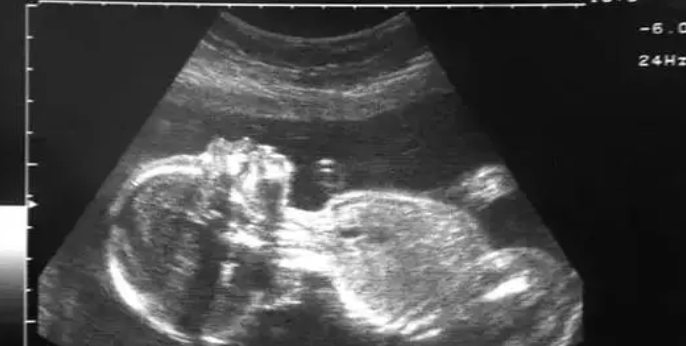

b超是一种常见的医学检查方法,可以通过超声波成像技术来观察胎儿在子宫内的发育情况。很多准父母都会翘首以待,想要早日知道自己的宝宝是男是女。那么,b超怎么看出是男是女呢?本文将带您了解几个识别宝宝性别的指标。

另外一个可以通过b超检查来判断宝宝性别的指标就是小便器官。男胎的小便器官相对女胎较为明显,通常在b超检查中可以清晰地看到一个“小鸡鸡”,而女胎则看不到这样的明显标志。

在b超检查中,医生还可以观察胎儿的发育特征来初步判断宝宝的性别。男胎的耻骨上突(在男性受精卵的受精中,出现着丸的原始起源“火山”)比较醒目,而女胎则不太明显。在13-14周的胎儿发育阶段,如果能够观察到外生殖器的胚芽膨起,也较好地证明了宝宝的性别。